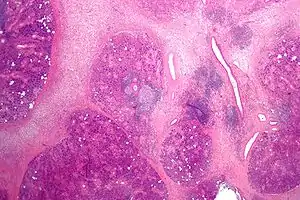

The gland is internally divided into lobules. Blood vessels and nerves enter the glands at the hilum and gradually branch out into the lobules.

Acini

Secretory cells are found in a group, or acinus. Each acinus is located at the terminal part of the gland connected to the ductal system, with many acini within each lobule of the gland. Each acinus consists of a single layer of cuboidal epithelial cells surrounding a lumen, a central opening where the saliva is deposited after being produced by the secretory cells. The three forms of acini are classified in terms of the type of epithelial cell present and the secretory product being produced - serous]], mucoserous, and mucous.[17][18]

Ducts

In the duct system, the lumina are formed by intercalated ducts, which in turn join to form striated ducts. These drain into ducts situated between the lobes of the gland (called interlobar ducts or secretory ducts). These are found on most major and minor glands (exception may be the sublingual gland).[17]